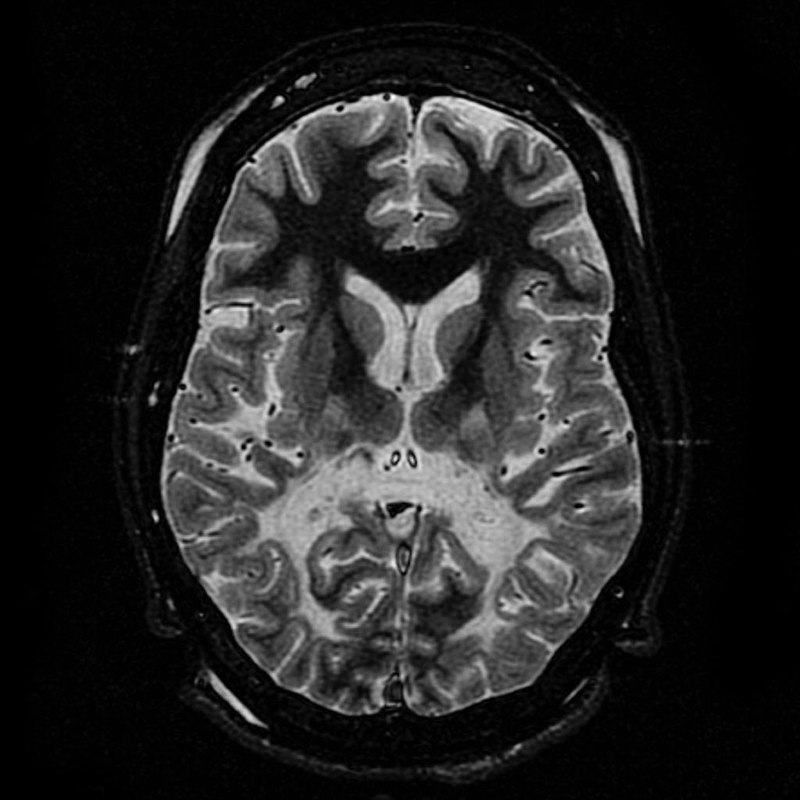

Magnetic resonance imaging (MRI) identifies plaques (areas of white matter demyelination) associated with multiple sclerosis (MS).

Gross inspection of brains with multiple sclerosis (MS) reveal white matter plaques that appear gray.